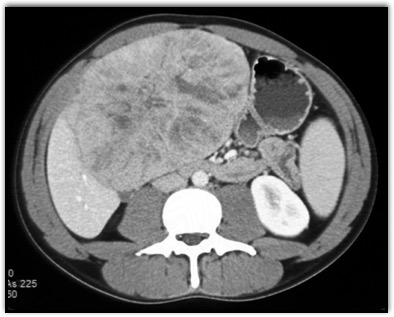

In this teenager the best diagnosis is?

CTisus Quiz   CTisus Quiz

FNH

hepatic adenoma

angiosarcoma of the liver

hepatoblastoma